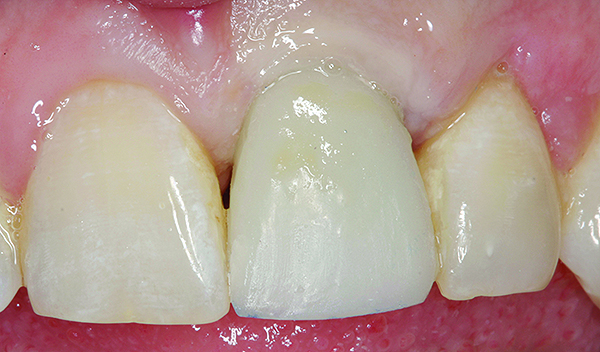

Fig 11. Preoperative photograph.

Figure 11

Fig 12. Postoperative photograph of patient shown in Fig 11 after immediate implant placement with immediate loading, tooth No. 9.

Figure 12

Achieving outstanding esthetics with implant dentistry is a reality (Figure 11 and Figure 12). Restorative efforts require disciplined steps to attain predictable results. To paraphrase my mentor, Cary Shapoff, DDS, renowned for his knowledge of periodontal disease treatment, bone grafting procedures, and dental implant surgery, implant esthetics is a series of well-planned, well-executed small steps that add up to a successfully restored fixture.